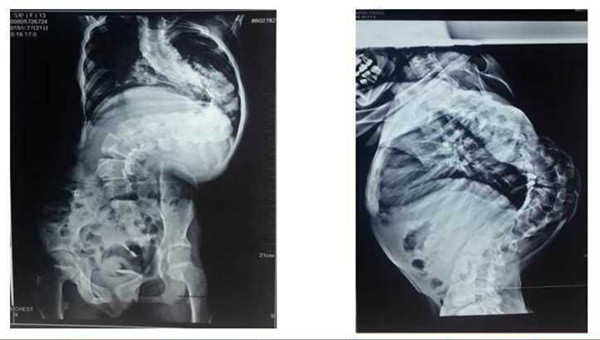

近日我院骨二科(脊柱外科)收治一例罕见的极重度脊柱侧后凸畸形患儿,13岁的女孩王某,十余年前无意间发现脊柱向侧后方弯曲,进行性加重,呈大驼背畸形,患儿家属辗转全国多家三甲医院就医,但均被告知风险及难度极大,而放弃治疗。直到今年7月才慕名到我院骨二科就医。接诊后,李浩鹏教授带领脊柱外科团队讨论病例,认为:患儿脊柱向外成角>160度(Cobb角超过160度),脊柱严重畸形、椎旁肌肉僵硬、胸廓畸形。如果采用直接手术矫形的方式,手术难度与风险极大。为了确保患儿安全及保护神经功能,最终决定运用渐进的方式进行治疗。首先采用头颅及双下肢骨牵引术,即在头顶两侧使用颅骨牵引架向上牵引,在双下肢胫骨踝上打克氏针向下牵引,通过上下两个方向同时逐渐牵引拉,将弯曲礓硬的脊体牵长、拉软,为手术做好准备。在持续牵引2周后,胸廓畸形、椎旁肌肉僵硬等情况得到较大改善,身长由130增加到145厘米。牵引过程中,孩子基本是固定在床上,很痛苦,但为了手术的顺利进行,患儿和家长都非常配合。